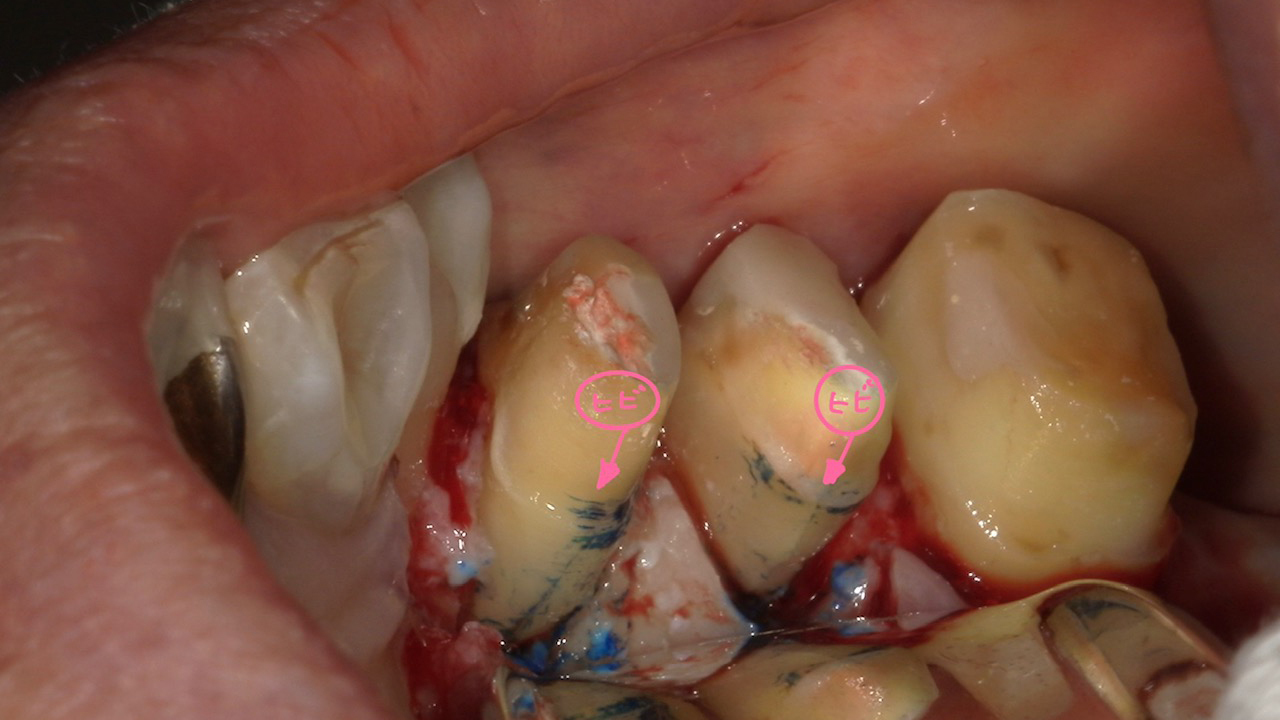

診断的フラップ手術

名古屋市名東区の自費の根管治療

歯茎を切開して、歯の根っこの状態を直接確認する手術方法です。

特にひび割れの診断は、この手法でしか確実には分からないケースが多々あります。診断的フラップ手術を行えば、より正しい判断で歯を守ることが可能になります。

他にも歯周病の有無や、歯質の残存量などを確認し、根管治療をして治せる可能性があるのか、残せたとしても歯として長期的に機能させられるかを総合的に診断し、何が患者様に最適かを一緒に考えます。

また、マイクロスコープを用いた精密な検査を実施。根管治療を行うべきか否かという判断も含め、多角的で丁寧な診査・診断を行っています。